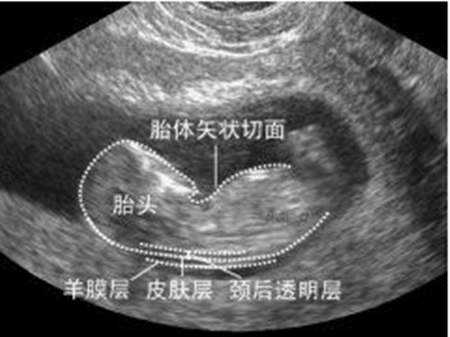

2、怀孕12周左右需要做NT检查,这个记得是需要空腹的。NT是妊娠早期胎儿畸形的筛查指标,也用于胎儿早期唐氏综合征的风险评估。我们是春节期间因为疫情的原因没法回北京所以就没有做;